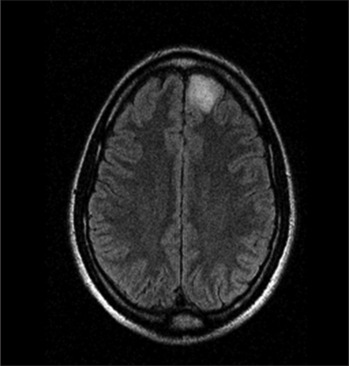

Behind the veil: Glioma presenting as delusional disorder.